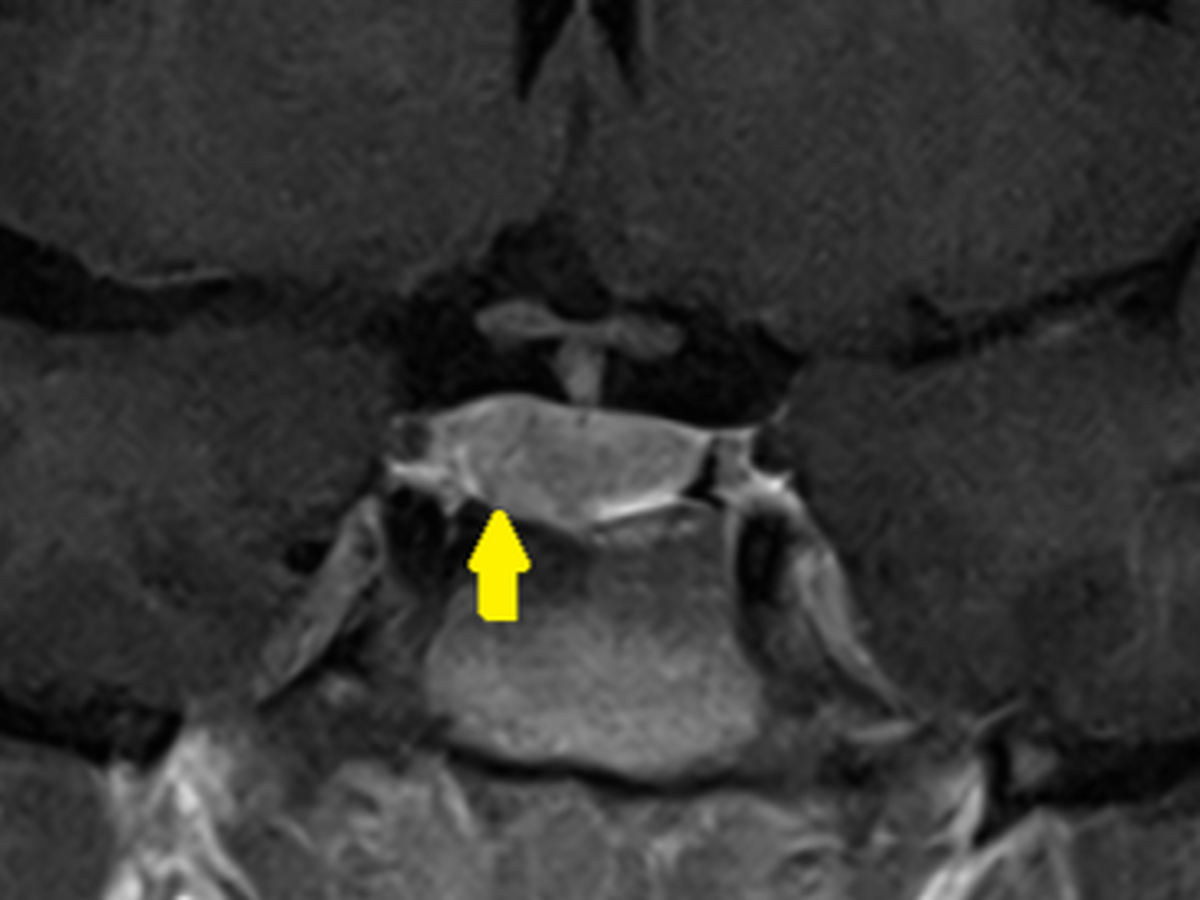

On November 14th 2024 I was informed that I have a 0.7cm Microadenoma inside my pituitary gland. The pituitary gland is a 1cm organ inside of the brain that produces several hormones, including prolactin. Prolactin is the primary hormone that my tumor has been affecting that has been causing my severe symptoms.